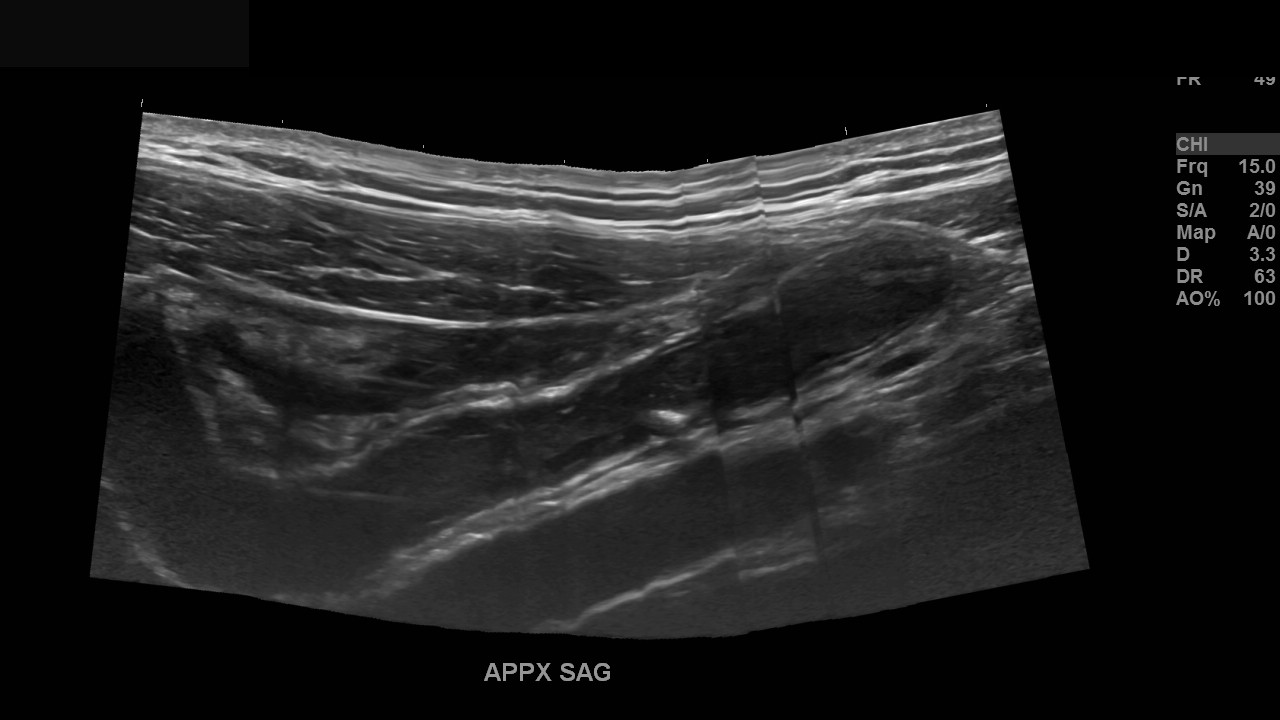

Appendicitis 13

Acute appendicitis @ 1 cm with L2-9mhz and L6-24mhz transducer GE Logiq e10.